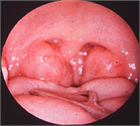

1. 睡眠時無呼吸症候群(SAS)とは睡眠関連呼吸障害(sleep related breathing disorder:SRBD)に含まれる病態である。いびきや睡眠中の無呼吸、日中の傾眠などを主訴とする疾患であり、2014年に改訂された睡眠障害国際分類第3版(ICSD-3)では主に睡眠中の気道、主に咽頭が完全または不完全に虚脱することが原因の閉塞性睡眠時無呼吸(Obstructive Sleep Apnea:OSA)と呼吸努力を伴わない中枢性睡眠時無呼吸症候群、睡眠関連低換気障害、睡眠関連低酸素血症に大別される。